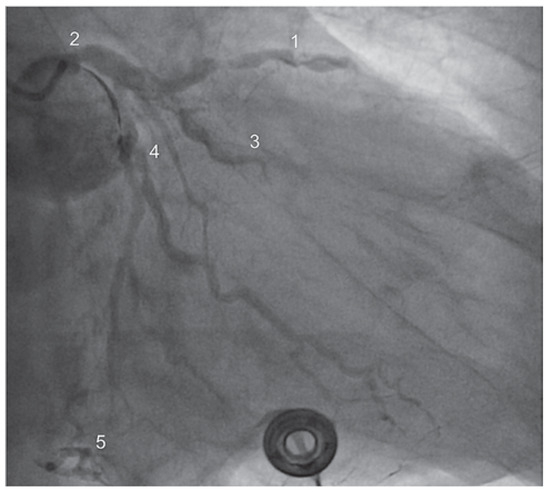

Case report A 22-year-old male experienced a presyncopal spell while studying for a university examination [...]